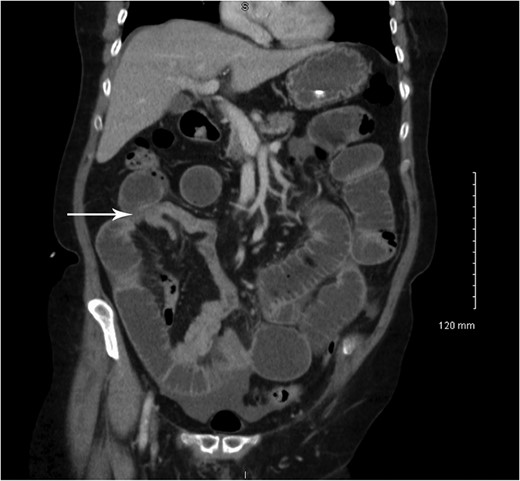

Coronal CT showing small bowel to small bowel intussusception (arrow).